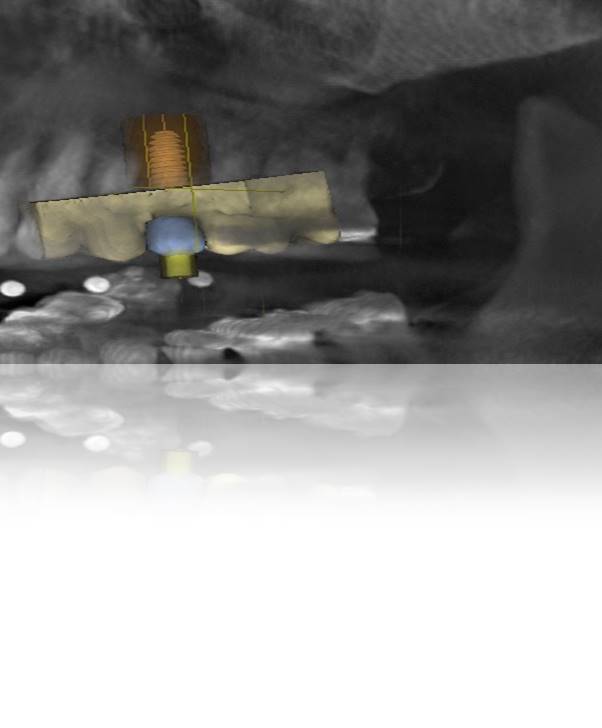

Therefore, pre-planning multiple aspects of the implant treatment, as well as the different components of the restoration, can help to ensure precise placement and angulation, as well as proper fit and connection of the implant abutment and restoration.19,20 Implant position, angulation, and restoration margin placement can be ideally planned based on preoperative analysis (eg, CBCT, planning software), and the anticipated outcomes achieved using surgical templates, guided surgery, and virtual/traditional restoration models (Figure 1 through Figure 7).21

Figure 3. However, simply delegating implant placement to the surgeon—without having the end in mind—may result in implant placement at the improper angulation.

Figure 3

Figure 4. View of the correctly planned and properly proposed implant placement, taking into consideration angulation and position for the anticipated screw-retained abutment/restoration.

Figure 4

Figure 5. Note that even slightly changing the angulation would result in the implant screw-access hole coming out of the buccal cusp.

Figure 5

Figure 6. View of the digitized treatment plan, illustrating implant angulation, restoration placement, and access hole alignment if original plan is altered.

Figure 6

Figure 7. View of the corrected treatment plan, illustrating proper implant angulation, ideal restoration placement, and correct access hole alignment/location.

Figure 7